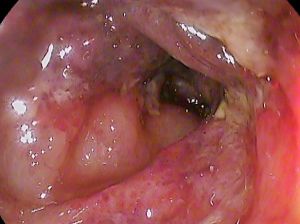

- Diagnosis is typically determined on abdominopelvic CT

- Ischemic colitis most likely when found in splenic flexure or sigmoid colon. Ischemic colitis unlikely for colitis that localizes to other areas

- Need follow up colonoscopy in months to ensure no underlying etiology.